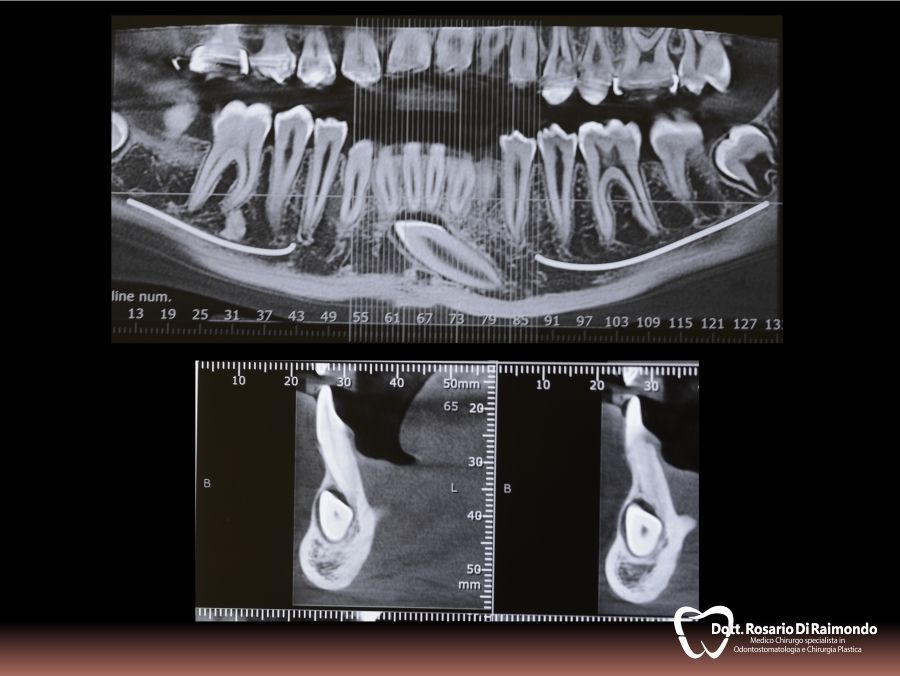

Estrazione del dente del giudizio

La rimozione del dente del giudizio, tecnicamente chiamata disodontiasi degli ottavi, è uno dei trattamenti principali della chirurgia odontoiatrica. Le indicazioni per l’estrazione del dente del giudizio sono molteplici: terzo molare con insufficiente spazio per erompere completamente o posto in una posizione anomala (comunemente detto dai pazienti “dente del giudizio storto”), indicazione da parte dell’ortodontista per l’allineamento dei denti in mancanza di spazio nelle arcate dentarie, presenza di profonde carie del dente del giudizio e infine estrazione strategica per evitare problemi nel molare adiacente.

Anche se i pazienti a volte riferiscono di avere il dente del giudizio infiammato, nella maggior parte dei casi i denti del giudizio non causano sintomatologia. Tuttavia, si può manifestare facilmente un'infiammazione della gengiva con dolore del dente vicino che prende il nome di pericoronarite. Inoltre è anche possibile che la mancata eruzione del molare del giudizio (e di conseguenza incluso nell’osso) causi cisti all’interno dell'osso. Sia la pericoronarite che le cisti associate ai molari del giudizio possono causare dolore, gonfiore ed eventuale presenza di secrezione purulenta accompagnata da cattivo odore.

Casi Trattati

Di seguito riportiamo alcune fotografie di casi esplicativi di Chirurgia Orale.